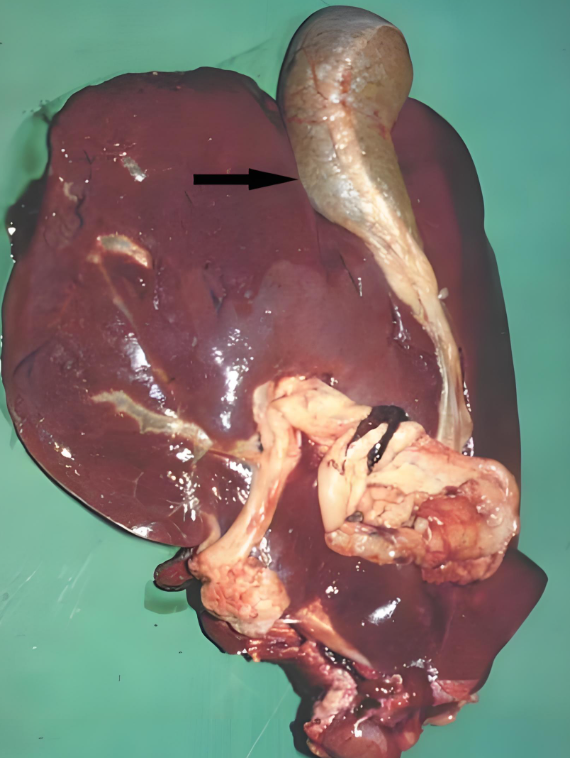

牛羊肝片吸蟲病診療指南:早識(shí)別、巧防控、準(zhǔn)用藥,守護(hù)養(yǎng)殖安全

對(duì)牧區(qū)和低洼地帶的養(yǎng)殖戶來(lái)說(shuō),牛羊肝片吸蟲病是常年懸著的 “隱患”—— 它不僅是牛羊的 “健康殺手”,導(dǎo)致消瘦、產(chǎn)奶下降甚至死亡,還是人畜共患病,人若生食受污染的水生植物、魚蝦也可能感染。掌握這種病的 “識(shí)別 - 防控 - 治療” 全流程,是養(yǎng)殖戶減少經(jīng)濟(jì)損失、保障養(yǎng)殖安全的關(guān)鍵。本文結(jié)合臨床實(shí)踐,拆解牛羊肝片吸蟲病的科學(xué)應(yīng)對(duì)方案,讓養(yǎng)殖戶能 “看得懂、用得上”。

一、先識(shí)病:搞懂病因與癥狀,避免延誤最佳處置時(shí)機(jī)

肝片吸蟲病的發(fā)生有明顯規(guī)律,癥狀也分急慢性,只有摸透這些特點(diǎn),才能在發(fā)病初期及時(shí)干預(yù)。

1. 病因:夏秋高發(fā),這 3 個(gè) “風(fēng)險(xiǎn)點(diǎn)” 要警惕

肝片吸蟲病主要在6-9 月夏秋季節(jié)爆發(fā),核心傳播鏈圍繞 “蟲卵 - 椎實(shí)螺 - 牛羊” 展開(kāi),3 個(gè)關(guān)鍵風(fēng)險(xiǎn)點(diǎn)需重點(diǎn)規(guī)避:

• 傳播媒介:椎實(shí)螺:這種螺是肝片吸蟲的中間宿主,只要水塘、沼澤里有椎實(shí)螺,就可能滋生肝片吸蟲囊蚴;

• 感染途徑:吃了帶囊蚴的水草:牛羊在低洼、沼澤地放牧?xí)r,誤食附著囊蚴的水草,囊蚴會(huì)進(jìn)入體內(nèi),最終寄生在肝臟;

• 易感群體:羔羊、綿羊風(fēng)險(xiǎn)最高:雖然各年齡、品種的牛羊都可能感染,但羔羊和綿羊感染后病死率更高,成年牛羊多表現(xiàn)為慢性癥狀。